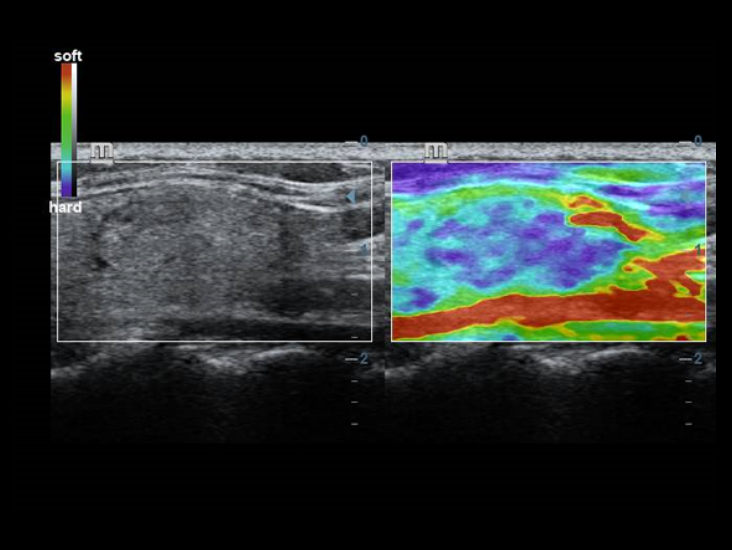

Klasyczne technologie obrazowania: zwi?kszenie jako?ci w diagnostyce

Poprzez zastosowanie klasycznych technologii obrazowania, wykorzystywanych w uznanych systemach ultrasonograficznych, DC-40 Full HD dostarcza doskonale szczeg├│?owy obraz.

W porównaniu z tradycyjnymi g?owicami, w g?owicach ComboWave zastosowano nowy typ kompozytowego materia?u piezoelektrycznego, aby uzyska? znacz?c? optymalizacj? spektrum akustycznego i zredukowa? impedancj? akustyczn?. W po??czeniu z unikaln? technologi? 3T Mindray, g?owice liniowe ComboWave pozwol? uzyska? wysokiej jako?ci obrazowanie o doskona?ej rozdzielczo?ci i jednorodno?ci w badaniach tarczycy, piersi, naczyń krwiono?nych i innych.